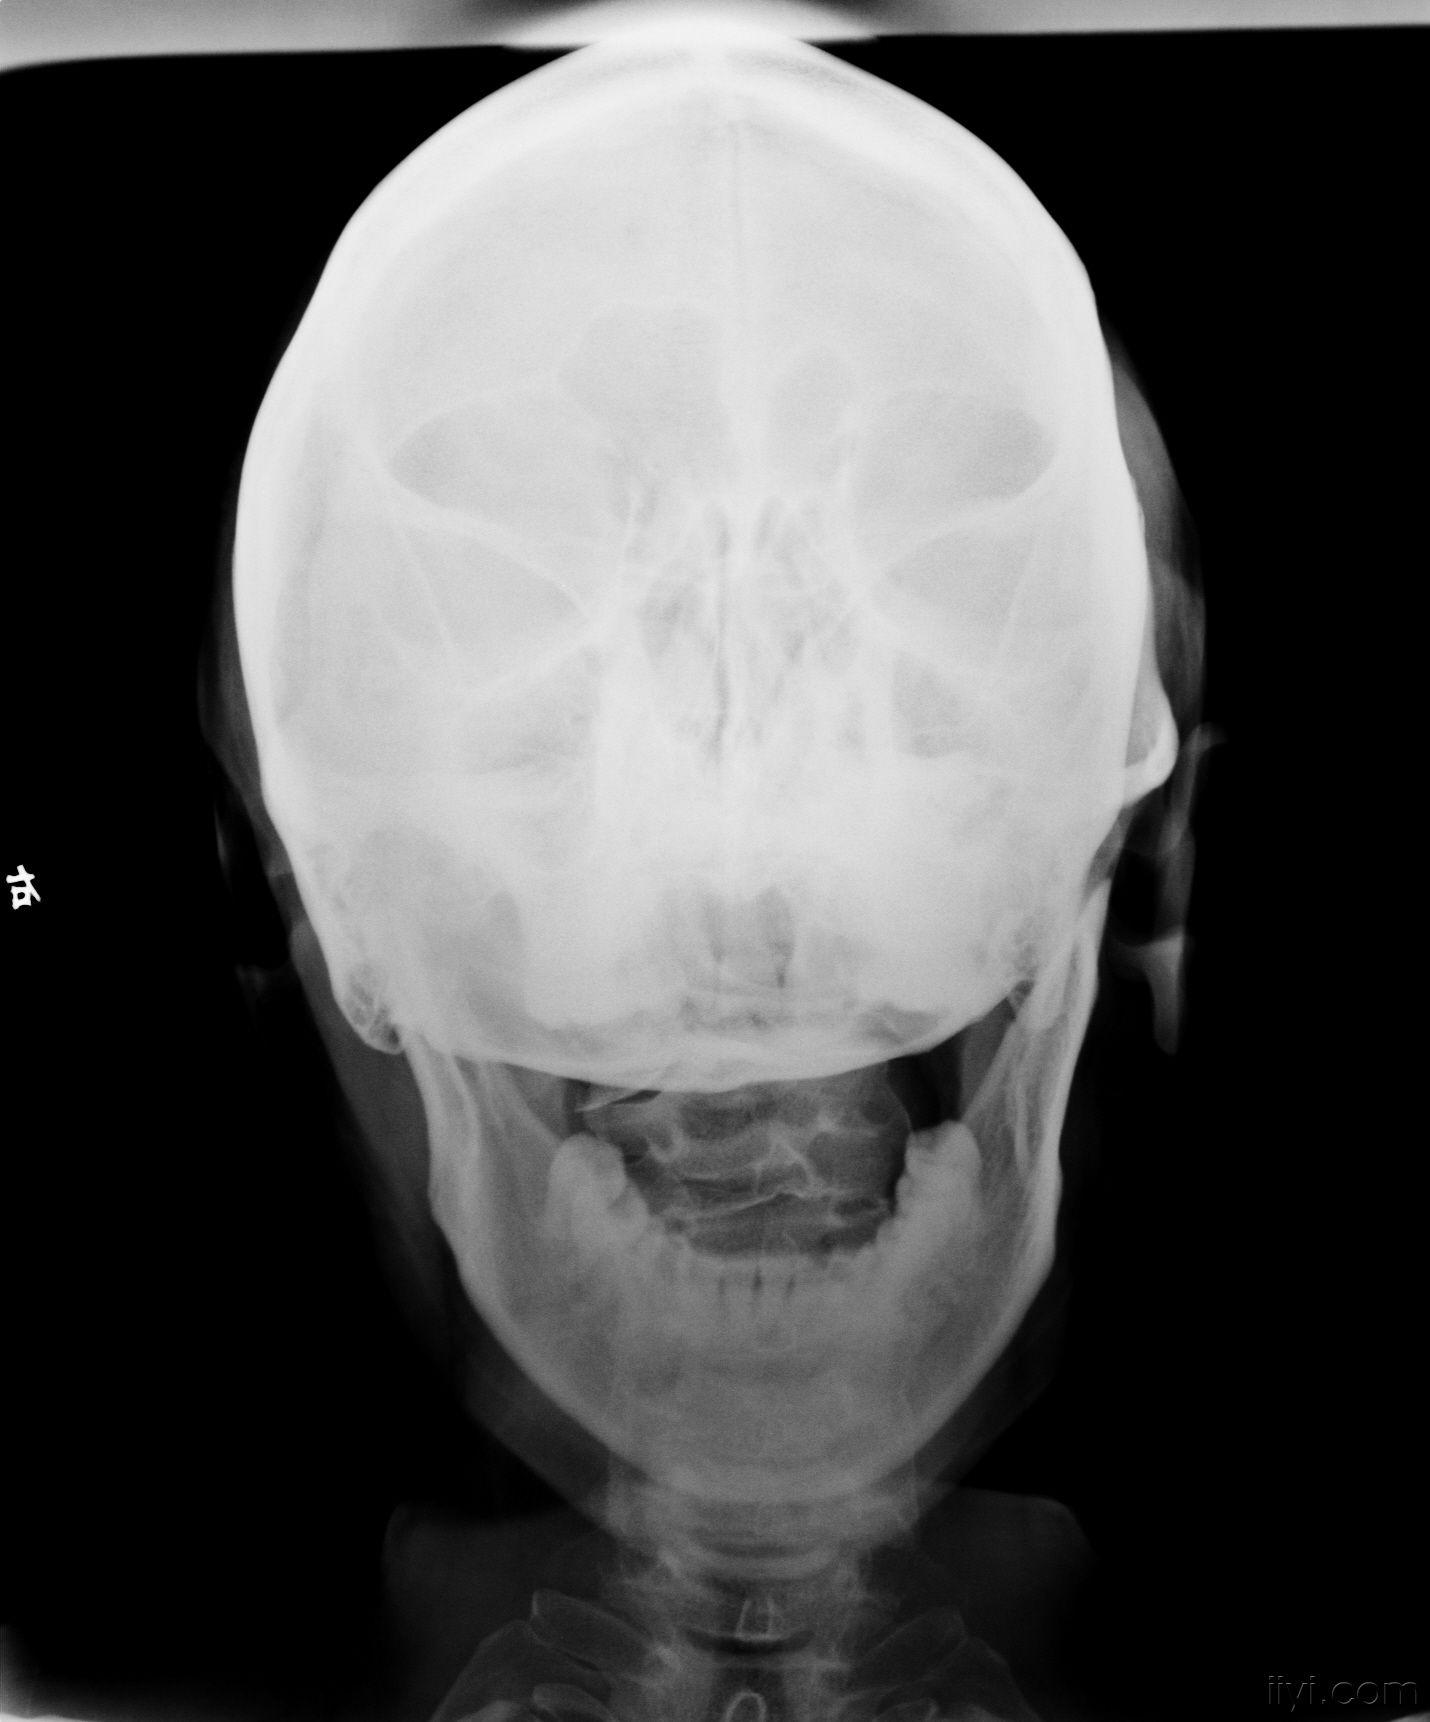

寰枢椎x片

x片

图片尺寸1430x1722

寰枢椎半脱位(dr)

图片尺寸1200x1600